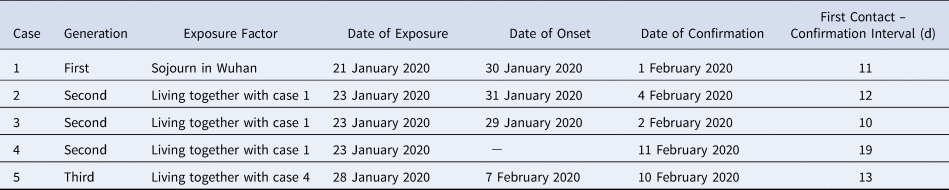

To better understand the transmission characteristics of COVID-19 outside Wuhan city, we carefully clarified the contact history of each case. Case 1 was a 56-year-old woman who had a history of travel to the city of Wuhan, Hubei province, on 21–22 January 2020 (Table 2 and Fig. 1). On 22 January 2020, case 1 returned to Dazhou and stayed with her mother (case 2), daughter (case 3) and daughter-in-law (case 4) from 23 to 27 January 2020. Case 1 developed fever and cough on 30 January 2020. On 28 January 2020, before case 1 showed any symptoms, case 4 had dinner and stayed with her mother (case 5). Cases 2–5 were all local Dazhou residents who had no history of contact with any patient with confirmed or suspected COVID-19 in the previous 14 days. On 1 February 2020, case 1 visited the hospital and tested positive for SARS-CoV-2 infection. The Dazhou CDC responded immediately and put case 1's family members (cases 2–5) in isolation, and they underwent epidemiological investigations and nucleic acid tests. Case 2, 3 and 5 successively developed fever, cough and fatigue symptoms, and were declared positive for SARS-CoV-2 infection on 4, 2 and 10 February, respectively. The nucleic acid test was also positive for case 4. however, she had no symptoms of infection, even during hospitalisation. As an asymptomatic patient, case 4 had transmitted the virus to case 5. This cluster demonstrated the existence of a three-generation transmission chain (Table 2). Of note, one asymptomatic case was found in this study.

Fig. 1. Relationship between the course and transmission of one case in familial cluster outbreak.

Table 2. Familial cluster outbreak of five COVID-19 cases